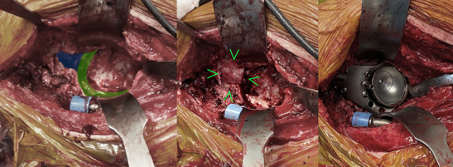

Intraoperative procedure

The key for preparing a successful implantation of the revision implant system is the removal of the indwelling components as well as extensive debridement and exposure of the bone defects. Any remaining connective tissue membranes and abrasion granuloma can result in repeated premature loosening and to implant failure as a consequence. Fig. 10 shows the prepared site after complete implant removal, debridement and cleaned up defects. As with the perioperative analysis and planning, this reveals a large defect spanning the superolateral to dorsal area of the acetabular rim, consistent with a Type 3 C ADC. In addition, there is a defect of the iliac bone which could not be evaluated pre surgery.

The surgical revision is once more performed in accordance with the therapeutic ADC algorithm [5]. A modular support cup is chosen as a revision system. The large acetabular rim defect is addressed with macroporous titanium augmentation, which exerts a direct transfer of forces onto the remaining bone substance. It is screwed onto the modular revision support cup system having been press-fitted with precision. Bone defects are augmented with biological material using impaction bone grafting outside of the loadbearing areas of the acetabular rim. Half a femoral head is used as a strut-graft analogue to augment the ileum defect. It is important here to separate it from the structural allograft in the load-bearing zone; in the literature this only shows a poor healing rate and high failure rates [11–14]. In this case, however, the main force is transferred onto the healthy bone by the metallic augmentation. The modified strut allograft is only used to seal the impaction bone grafting. Then the construction is fixated with 2 acetabular dome screws with good tension and several dynamic hip screws and flanged screws with a stable angle. The acetabulum itself can only be tensioned in the primary stable implanted modular support cup with adjustable inclination and anteversion.